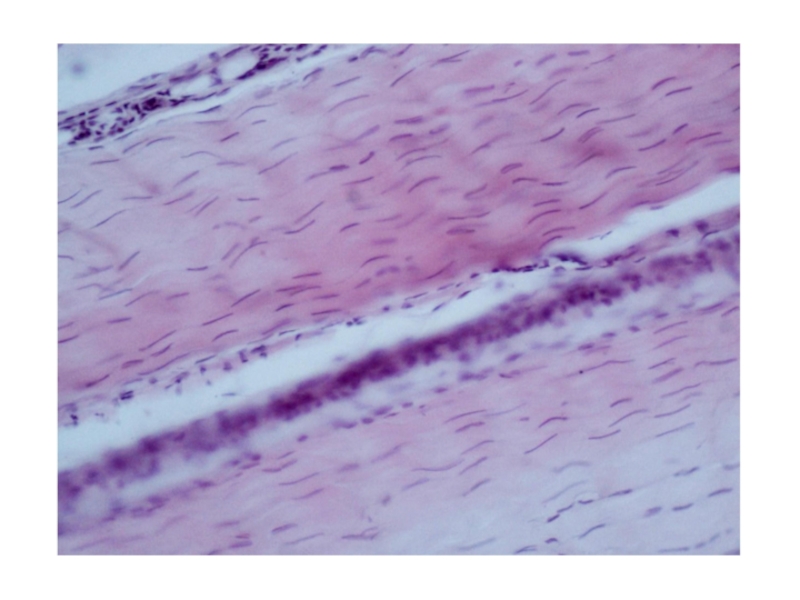

Слайд 29Препарат №62 «Плотная волокнистая оформленная соединительная ткань.

Сухожилие. Продольный срез»

Препарат №62 «Плотная волокнистая оформленная соединительная ткань. Сухожилие. Продольный срез»